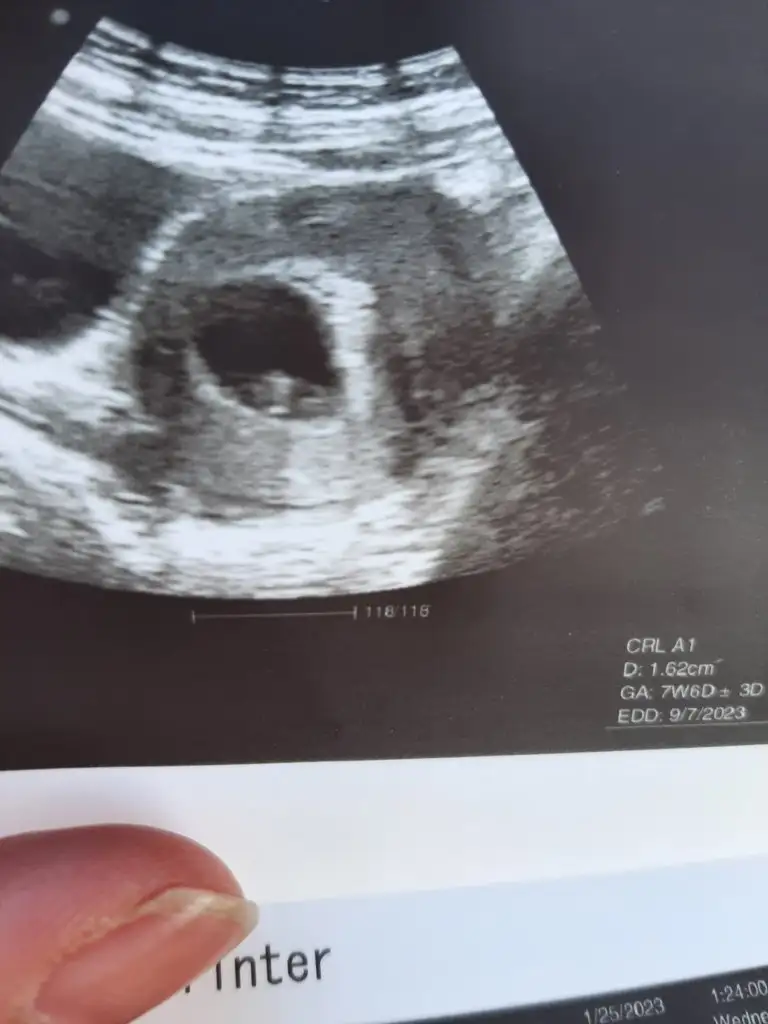

Benimkine yorumlarısınız 9+2 haftalıkBen nubdan bakmıyorum canım ama 6-9 haftalık görüntüsü varsa yorumlarım :)

Meraba benimki 9+2haftalik cinsiyet tahmininde bulunurmusunuz acaba6-9 haftalık fotosunu atarsanız yaparım burda bebişiniz çok büyük böyle bilemiyorum maalesef

Görüntü çok iyi değil emin değilim ama erkek gibi. 7 haftalık görüntüsü varsa atarsanız bakalım yineBenimkine yorumlarısınız 9+2 haftalık

Burda 8 haftalıkMerhaba burda bebişiniz büyük yorum yapmam için 6-9 haftalık ultrason görüntüsünü atarsanız iyi olur. Bu şekilde anlamıyorum maalesef :)

Karından ultrasonsa kız vajinal ultrasonsa erkek canımBurda 8 haftalık